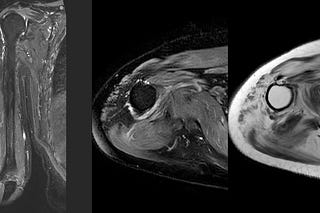

Case 58: A Milwaukee Shoulder in Mumbai

66-years old man with gradually progressive pain, without fever in the right shoulder.